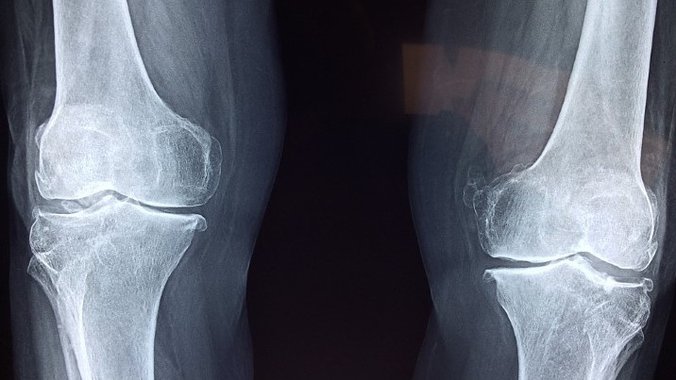

U mnogim sportovima kao što su trčanje, ragbi i fudbal, uvek postoji rizik od naprezanja zglobova kolena, kao i ostalih zglobova u organizmu. Intenzivni treninzi u navedenim, a i mnogim drugim sportskim disciplinama mogu oštetiti zglobove, i dovesti ih u opasnost od preloma, uganuća, bolova, sportskih povreda, pa čak i osteoartritisa.

Kod trčanja ili sportova koji zahtevaju puno trčanja, zglobovi se jako opterećuju, naročito u području kolena. Takođe, u sportovima gde dolazi do intenzivnog kontakta među igračima, zglobovi ramena i vrata su takođe osetljivi u vezi oštećenja.

Foto: Pixabay.com